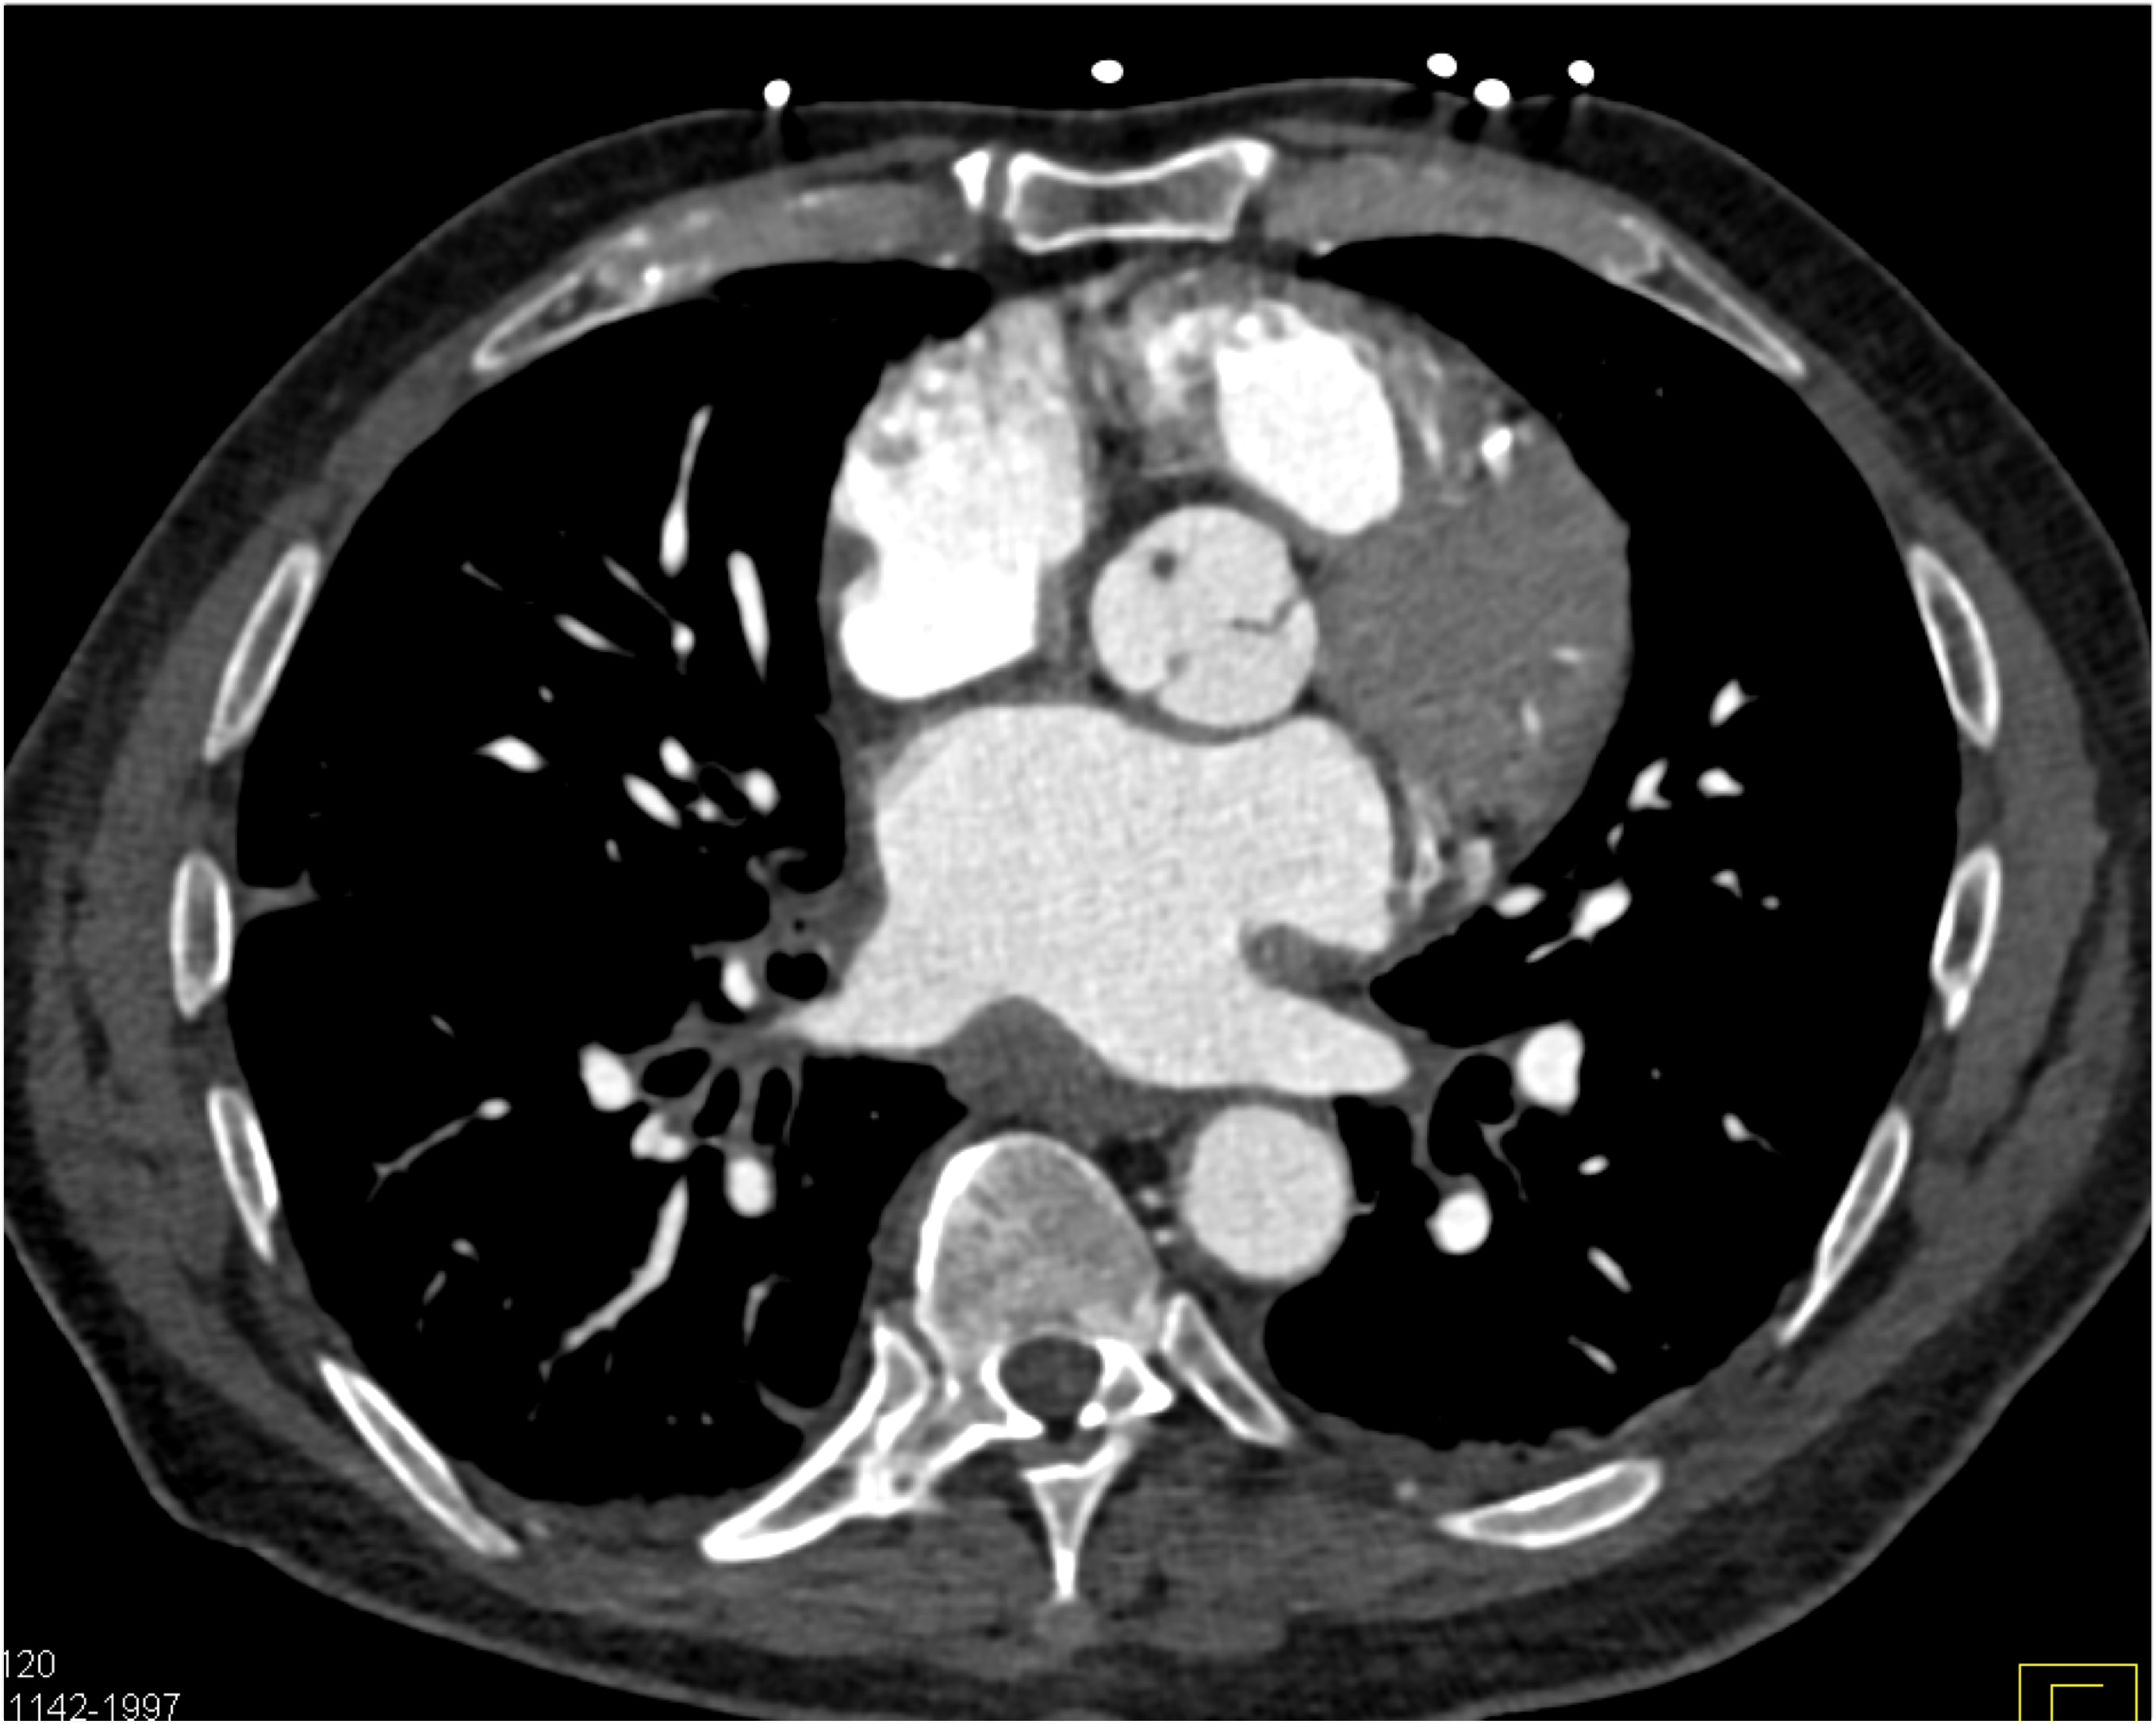

4) The most likely diagnosis in this patient with acute chest pain is?

type A dissection

intramural hematoma

type B dissection

Takayasu’s aortitis